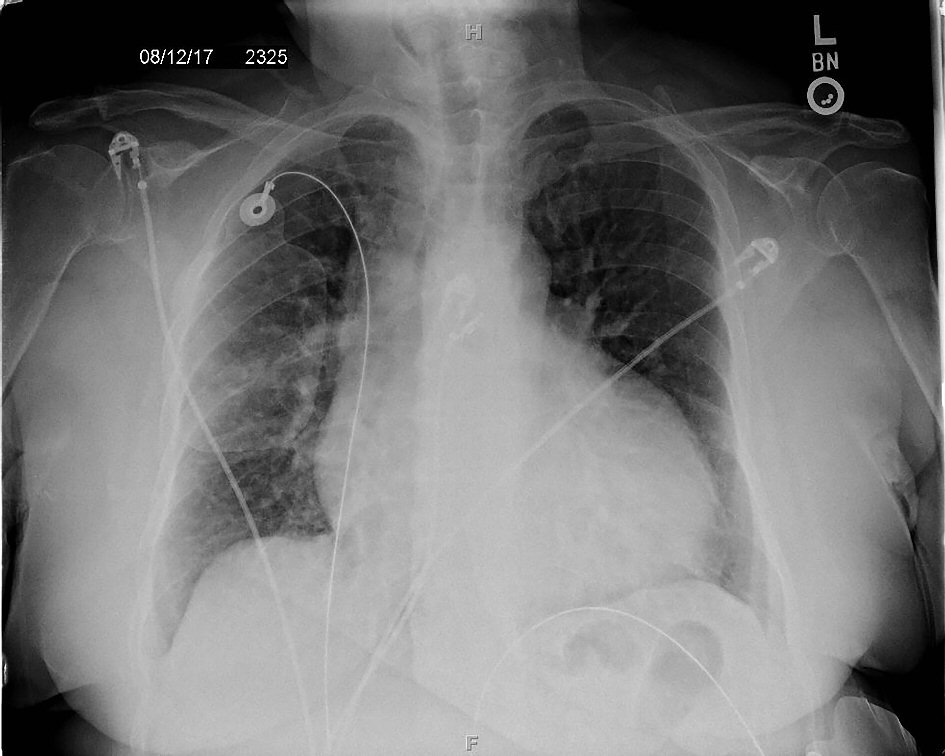

Figure 2. Posterior-anterior chest X-ray showing enlarged cardiac silhouette and vascular congestion.